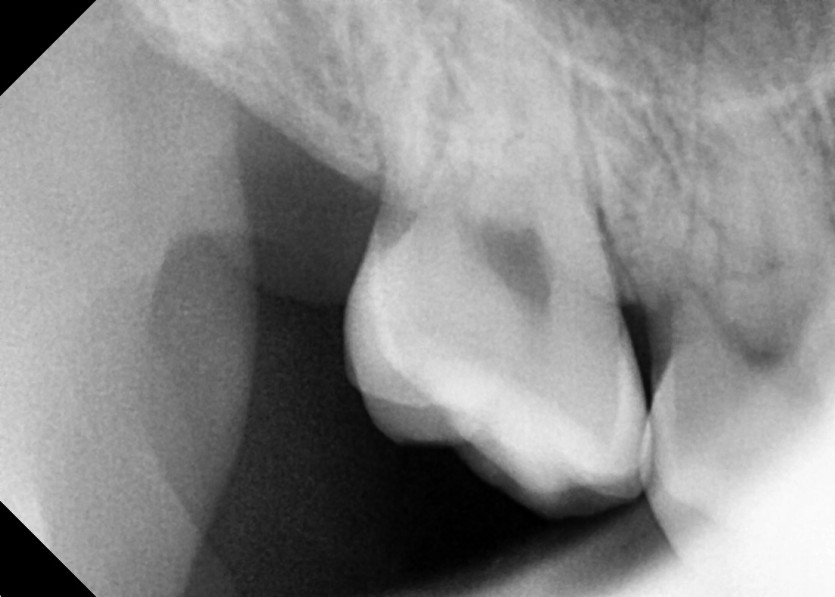

#18,48 사랑니 발치

구강 외과 전문의가 당일 발치했습니다.